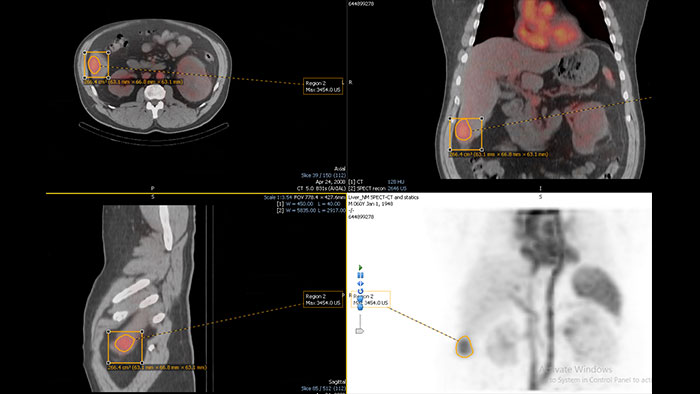

Enhanced user experience for NM reading with a leading NM viewing solution

A comprehensive NM solution, designed to enhance productivity of PET/CT and NM reading. It offers a solution for handling multiple studies requiring rigorous quantification of MV data**.

Benefits